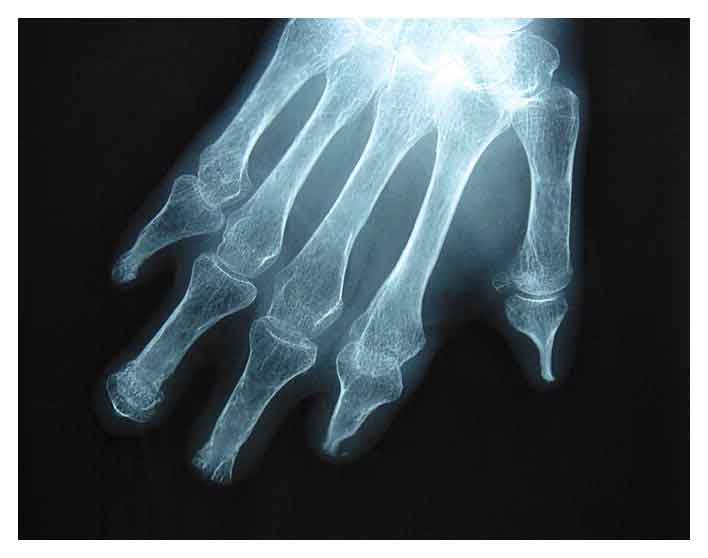

Sono incoraggianti i primi risultati di uno studio internazionale sul trapianto di cellule staminali ematopoietiche contro la sclerosi sistemica cutanea diffusa, una malattia autoimmune rara ma molto grave. Il trial di fase III e’ stato presentato all’Eular 2012 (Lega europea sulle malattie reumatiche) di Berlino da Jaap van Laar della Newcastle University (Gb).

I dati indicano che il trapianto di staminali ematopoietiche e’ legato a risultati milgiori in termini di sopravvienza a lungo termine rispetto ai trattamenti convenzionali.

Lo studio ha coinvolto oltre 150 malati tra il 2001 e il 2009, divisi in due gruppi: uno e’ stato sottoposto al trapianto di ‘cellule bambine’, l’altro a trattamento con ciclofosfamide. A maggio 2012 si era registrato un numero di decessi “significativamente maggiore” nel secondo gruppo. “Questi risultati iniziali – commenta van Laar – sono moloto incoraggianti e ci aiuteranno a identificare i pazienti che possono beneficiare del trattamento con staminali”.